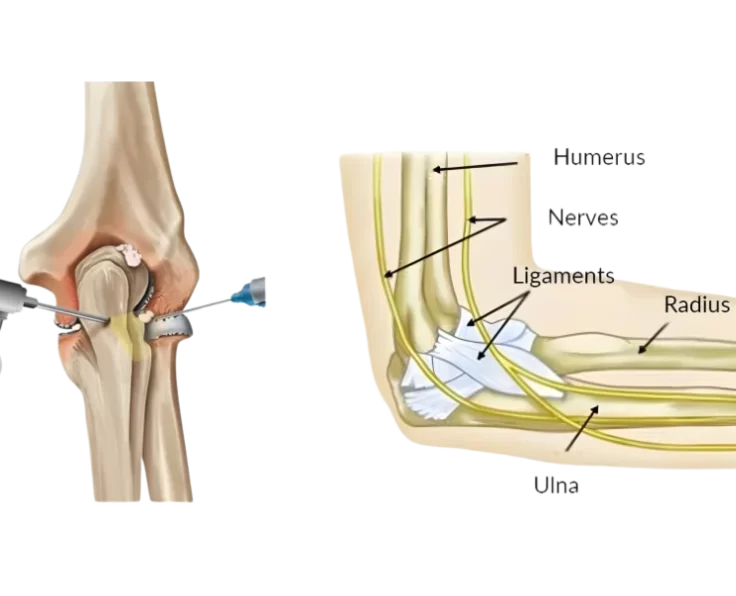

Elbow Arthroscopy

The term arthroscopy comes from Greek words that refer to the joint. In modern surgery, your surgeon uses a small camera and a video monitor…

Elbow Arthroscopy OK Procedure

The operation is used to alleviate pain, eliminate locking, and increase elbow joint mobility. We do this operation as an arthroscopic procedure, despite the fact…

Elbow Arthroscopic Capsular Release

Loss of motion in the elbow joint can be caused by a variety of factors, the most common of which is elbow trauma.

Elbow Arthroscopic Debridement

Arthroscopic debridement of the elbow is a treatment procedure used to examine, diagnose, and correct abnormalities within the elbow joint.

Elbow Arthroscopic Removal of Loose Bodies

Are you unable to totally bend or straighten your elbow? Do you have pain, stiffness, or a crunching or popping sound coming from your elbow?